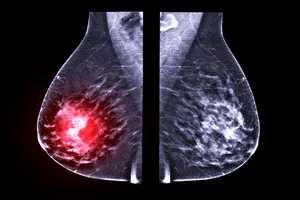

유방암은 여성에게 발생하는 가장 흔한 암 중 하나이며, 조기 발견과 치료가 매우 중요합니다. 초기 유방암은 대부분 증상이 없거나 미미하여 자각하기 어려울 수 있지만, 몇 가지 주의 깊게 살펴봐야 할 변화들이 있습니다. 오늘은 유방암 초기증상에 재해 알아보도록 하겠습니다.

- 40세 이상 여성은 1~2년마다 유방 X선 촬영(맘모그래피)을 받는 것이 좋습니다.

유방암을 예방하지는 못하더라도, 조기 발견을 통해 치료 성공률을 크게 높일 수 있습니다. 자가검진은 매달 한 번, 월경이 끝난 후 5~7일 사이에 정기적으로 실시하는 것이 좋습니다. 40세 이상 여성은 1~2년마다 유방 X선 촬영(맘모그래피)을 받는 것이 좋습니다. 유방암 가족력이 있는 경우, 30대부터 유방 초음파나 MRI 검사를 전문의와 상담 후 고려해 볼 수 있습니다.